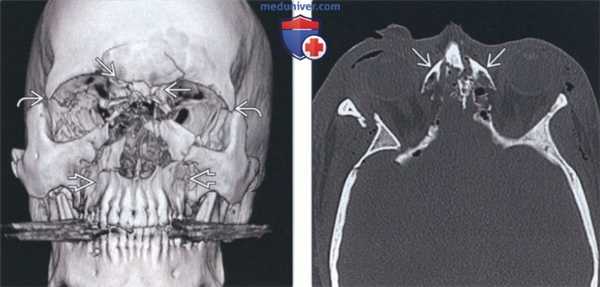

(Слева) На аксиальной КТ в костном окне определяется многооскольчатый перелом носо-глазнично-решетчатого (НГР) комплекса. Множественные мелкие фрагменты визуализируются в области внутренних углов глаз, присутствует телекантус. Определяется отек мягких тканей, эмфизема и перелом латеральной стенки глазницы.

(Справа) На более каудальной аксиальной КТ в коаном окне у этого же пациента определяется повреждение обоих носослезных протоков. В этом случае ожидаемым осложнением становится слезотечение.

(Слева) На трехмерной КТ-реконструкции определяется перелом НГР комплекса в области спинки носа. Переломы латеральной стенки глазницы и переломы верхней челюсти могут обнаруживаться у пациентов с переломами Ле Фор III и Ле Фор II соответавенно. При тяжелой травме лица наличие признаков более чем одного варианта - редкая находка.

(Справа) На аксиальной КТ в костном окне визуализируются доминирующие фрагменты медиальной стенки глазницы, прикрепленные к сухожилию внутреннего угла глаза. Такой перелом НГР (тип I по Мэнсону) характеризуется наилучшим постоперационным прогнозом.

(Слева) При КТ в аксиальной проекции определяются многооскольчатые переломы назо-орбито-этмоидального комплекса. В области медиальных связок век видны множественные мелкие костные отломки, отмечается телекант. Также наблюдаются отек мягких тканей, эмфизема и перелом наружной стенки глазницы.

(Справа) При КТ в аксиальной проекции (срез проходит ниже предыдущего) у этого же пациента видно, что при переломе повреждены оба носослезных канала. У таких пациентов травма осложняется слезотечением.

(Слева) При КТ в аксиальной проекции определяются оскольчатые переломы назо-орбито-этмоидального комплекса, вызвавшие западение спинки носа и перелом левой бумажной пластинки (lamina papyracea).

(Справа) При КТ (3D реконструкция) у пациента 20 лет определяются многооскольчатые переломы назо-орбито-этмоидального комплекса, глазницы и верхней челюсти.